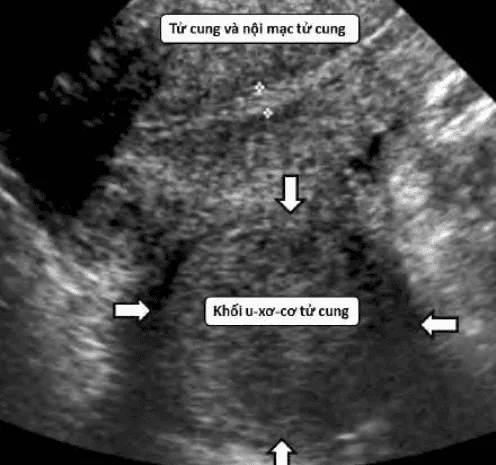

Phần tiêu đề “Cận lâm sàng”Siêu âm thang xám: Khối giảm âm, giới hạn rõ, bóng giảm âm sau.

Hình ảnh “U xơ tử cung trên siêu âm”.